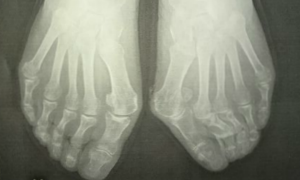

外反母趾は症状、変形、疼痛の痛みの具合は様々です。

外反母趾の問題は疼痛(とうつう)、痛みだけではありません。

・外反母趾の変形症状による身体を支える機能の低下、消失